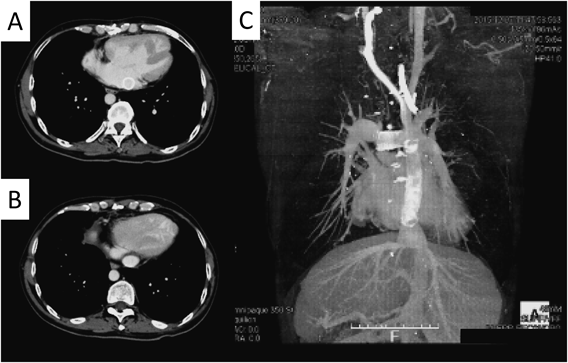

造影CT検査

心房心室ともに拡大所見を認めた.上下大静脈は心尖同側の左側心房に還流,肝静脈はすべて下大静脈に還流し,両側肺静脈は右側心房に還流していた.下大静脈の拡大所見を認めた(Fig. 3).以前施行された左体肺動脈短絡手術に用いられた人工血管は閉塞していた.3D-CTでは,肺動脈は蛇行屈曲を認め,左右肺動脈分岐部にも狭窄を認めた(Fig. 4).

Pediatric Cardiology and Cardiac Surgery 33(3): 249-255 (2017)

Fig. 3 Preoperative computed tomography (CT)

(A) Preoperative CT angiogram showing the superior vena cava located on the left side. (B) All pulmonary veins returned to the right side of the atrium. (C) Large atrium and dilated right ventricle. (D) Cardiac apex and inferior vena cava were located on the left side.